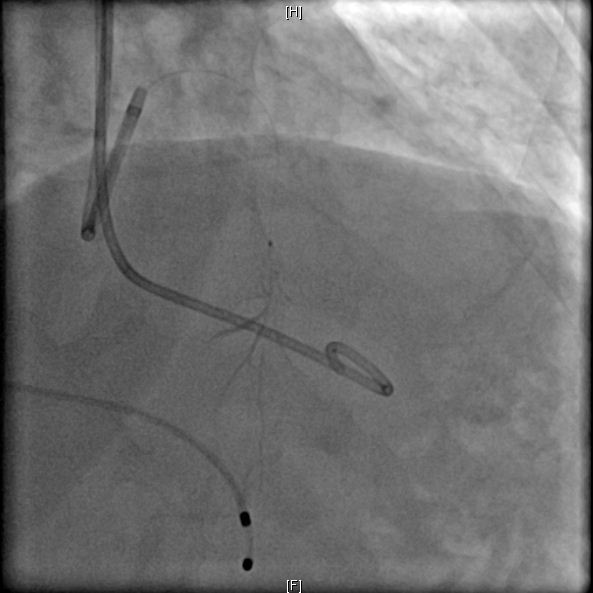

图: 冠状动脉第二间隔支S2粗大(左) 图: 造影示冠状动脉S2闭塞(右)